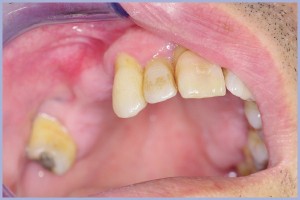

Paziente di anni 59, in buono stato di salute, ex-fumatore, con inadeguata igiene orale, si presenta nel mio studio riferendo sintomatologia dolorosa con una marcata parodontopatia degli elementi dentali, con protesi fissa incongrua dell’elemento dentale 1.4 e recessione gengivale con elemento 1.5 in estensione.

All’esame obiettivo, il paziente presenta mobilità di grado marcato dell’elemento dentale 1.4 con edema ed ascesso, e gengivite cronica necrotizzante con fuoriuscita di pus alla compressione. Si esegue OPT che rileva intorno alla zona radicolare dell’elemento dentale 1.4, vasta area di radio trasparenza, con riassorbimento degli apici radicolari e dell’osso verticale mesio-distale dell’elemento stesso. Si incide l’ascesso con Laser Nd-yag e si esegue lavaggio con una cefalosporina di terza generazione (Rocefin) e si lascia il drenaggio in permanenza con garza orlata iodata. Infine si congeda il paziente con terapia antibiotica ed antalgica.

- Fig. 2 – Situazione iniziale